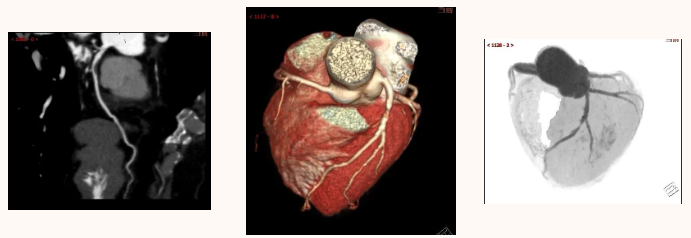

CT 血管造影(CTA),即 CT 血管成像,是一种利用计算机三维重建方法合成的非创伤性血管成像技术,可以在没有创伤的情况下,很好地了解身体中血管的情况。具有时间短、无创、特异性和敏感性高,时间和空间分辨率高等特点,能全方位显示出血管病灶,对于经其他检查已经明确患有血管疾病,需进一步了解病情严重程度具有重要的意义。

通过 CT 血管成像,可显示动脉病变,如血管闭塞、动脉瘤及夹层动脉瘤、血管畸形、血管损伤、心脏冠状动脉病变等。可进行冠心病 CT 筛查,冠心病术前、术后评估,脑卒中一站式检查,灌注成像等。

CTA 检查在大血管、外周血管疾病、心脏冠状动脉相关疾病、中枢神经系统疾病以及肿瘤疾病的诊断中发挥着重要作用。